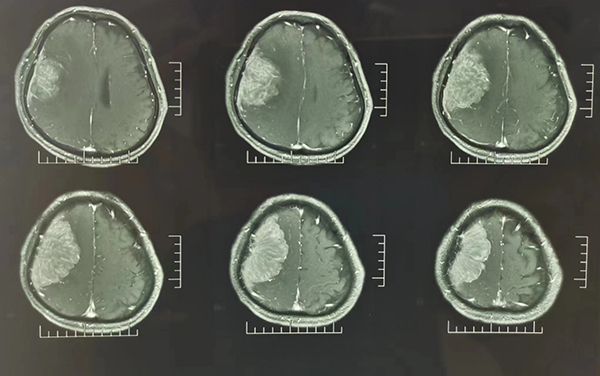

2周前,家住沛縣的劉老先生逐漸覺得左側(cè)胳膊腿有些麻木,開始以為年紀(jì)大了,有點(diǎn)輕微腦梗,也沒過(guò)多在意,可是后來(lái)癥狀越來(lái)越重,家里子女不放心,就帶他到當(dāng)?shù)蒯t(yī)院做了個(gè)檢查。不查不要緊,一查嚇一跳,CT和MR發(fā)現(xiàn)劉老先生顱內(nèi)長(zhǎng)了一個(gè)接近10cm的瘤子。當(dāng)?shù)蒯t(yī)生馬上介紹他到徐醫(yī)附院顱底腫瘤外科。

苗發(fā)安副主任醫(yī)師接診后,安排劉老先生住院進(jìn)一步完善了相關(guān)檢查,結(jié)果發(fā)現(xiàn)劉老先生顱內(nèi)長(zhǎng)了一個(gè)大小約10cm*8cm大小的腦膜瘤。腫瘤不僅僅體積大,位置也不好,壓在了右腦的運(yùn)動(dòng)區(qū),術(shù)后很可能會(huì)出現(xiàn)左側(cè)肢體偏癱等并發(fā)癥。診斷明確后顱底腫瘤外科主任范月超教授、梁君主任醫(yī)師組織科室進(jìn)行了手術(shù)方案的討論,結(jié)合患者年齡、癥狀,腫瘤大小、位置等,制定了周密的術(shù)前準(zhǔn)備和手術(shù)方案。